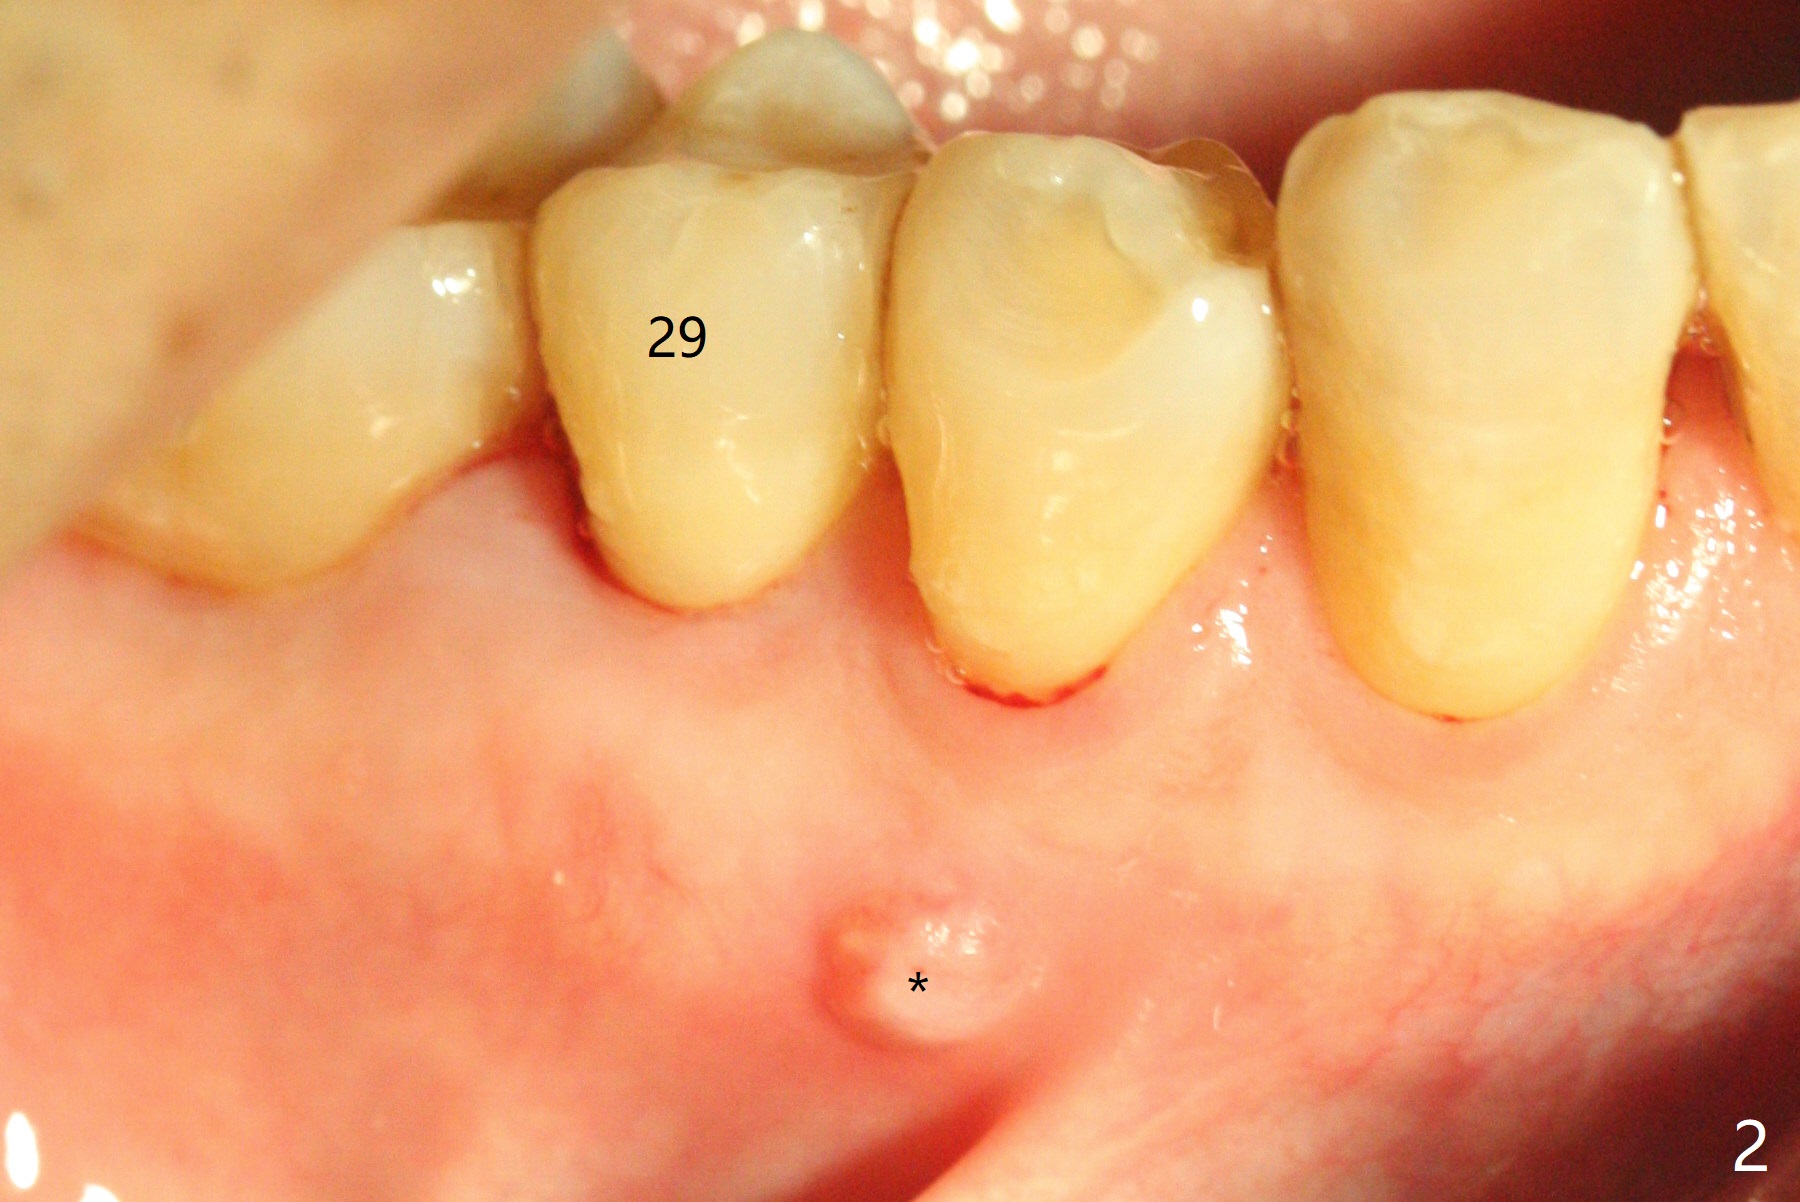

A 48-year-old man, dental phobic, wants minimal dentistry. The tooth #29 has large periapical radiolucency, extending mesial (Fig.1 *) and a fistula, apparently associated with the tooth #28 (Fig.2 *). The single canal has been debrided with 30/.06 rotary file and medicated with CaOH paste. To avoid microleakage without crown, gutta percha (Fig.3 white outline) will be cut apical to the distooclusal compostie (C). The fistula shrinks with no discharge 16 days post application of Calcium Hydroxide paste (Fig.4). RCT will be finished 2-3 weeks.